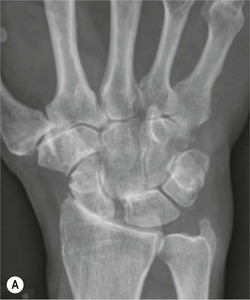

The mechanics of the wrist are complex, but movement occurs primarily through the proximal carpal row, comprising the scaphoid, lunate and triquetrum. This acts as a bridge between the forearm bones and the distal carpal row, which is relatively rigid. The proximal carpal row is referred to as the intercalated segment, and the lunate acts as the keystone. Stability between the segments of the proximal row is maintained by the intrinsic scapholunate and lunotriquetral ligaments. Stability between the radius and ulna, the proximal and distal carpal rows is maintained by multiple dorsal and volar extrinsic ligaments. Carpal alignment is assessed on PA radiographs, by identifying continuity of the articular surfaces of the carpal bones (known as the arcs of Gilula).

Tears of the ligaments of the wrist can result in carpal instability. Disruption of the intrinsic ligaments results in intercalated segment instability. This is also termed dissociative carpal instability because there is dissociation between the segments of the proximal carpal row.

The scapholunate ligament is most frequently involved. Radiographs may show scapholunate diastasis (>3 mm). The lunate demonstrates dorsal rotation on lateral views and volar rotation of the scaphoid. This results in an increase in the scapholunate angle (>60°) known as dorsal intercalated segment instability (DISI) (Fig. 46-27). A DISI deformity of the carpus may also be associated with fractures of the scaphoid.

More subtle degrees of instability may be demonstrated by an instability series of radiographs acquired with radial and ulnar deviation and with a clenched fist view. Video fluoroscopy is also useful for assessing dynamic wrist instability.